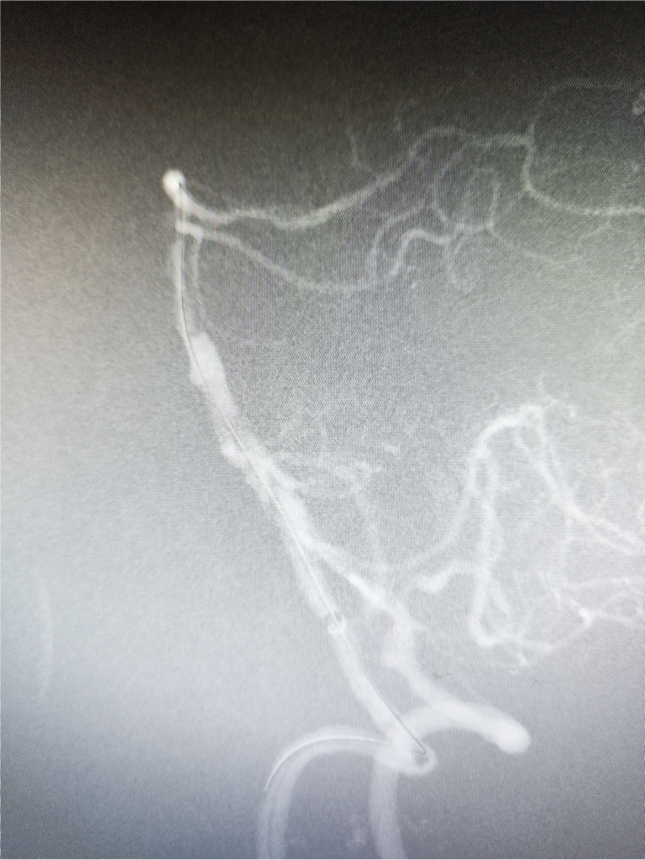

造影显示基底动脉远端闭塞,建立血管内治疗通路:Locaste长鞘同轴带领Skathi远端通路导管到位。

微导丝超选至右侧大脑后动脉,微导管通过狭窄段困难。考虑原位狭窄,行球囊扩张。

球扩后狭窄改善后不能维持,沿微导丝微导管通过狭窄段至右侧大脑后动脉,释放Enterprise2支架一枚。

狭窄改善明显,前向血流维持良好,mTICI分级3级